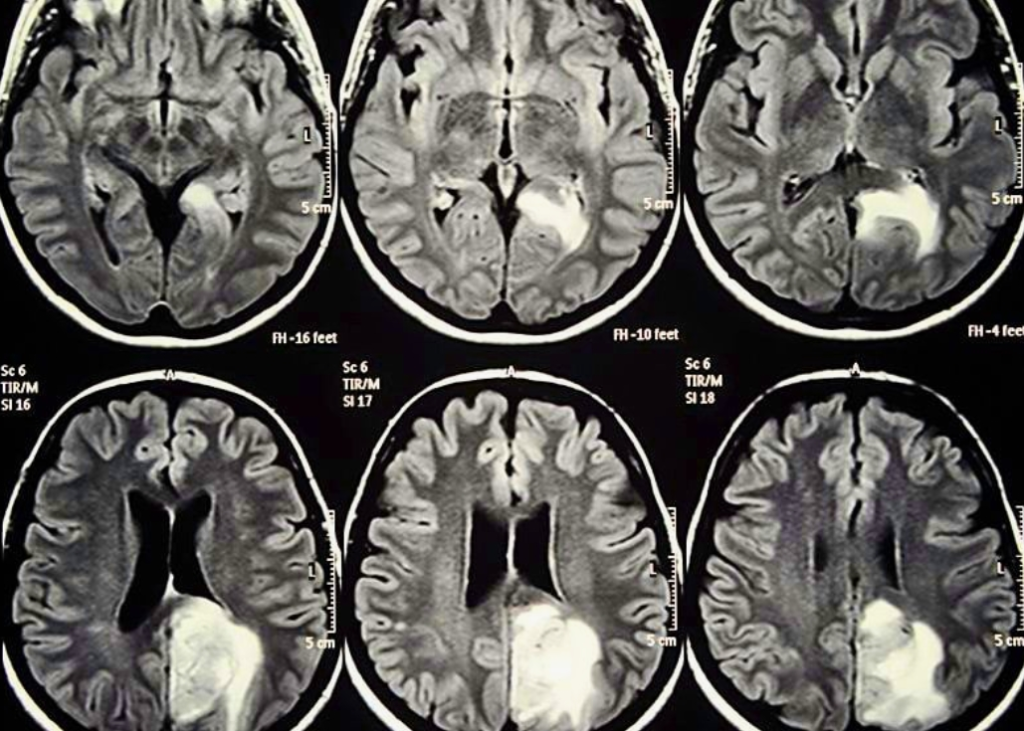

Then came the appointment we had been dreading and praying for all at once. The doctor looked at the scans again and again, as if he didn’t quite trust his own eyes. The tumor had shrunk by half. The nodules in her lungs were gone. Completely gone. I broke down right there in that cold, sterile room, unable to hold back the tears. Months of fear poured out all at once.